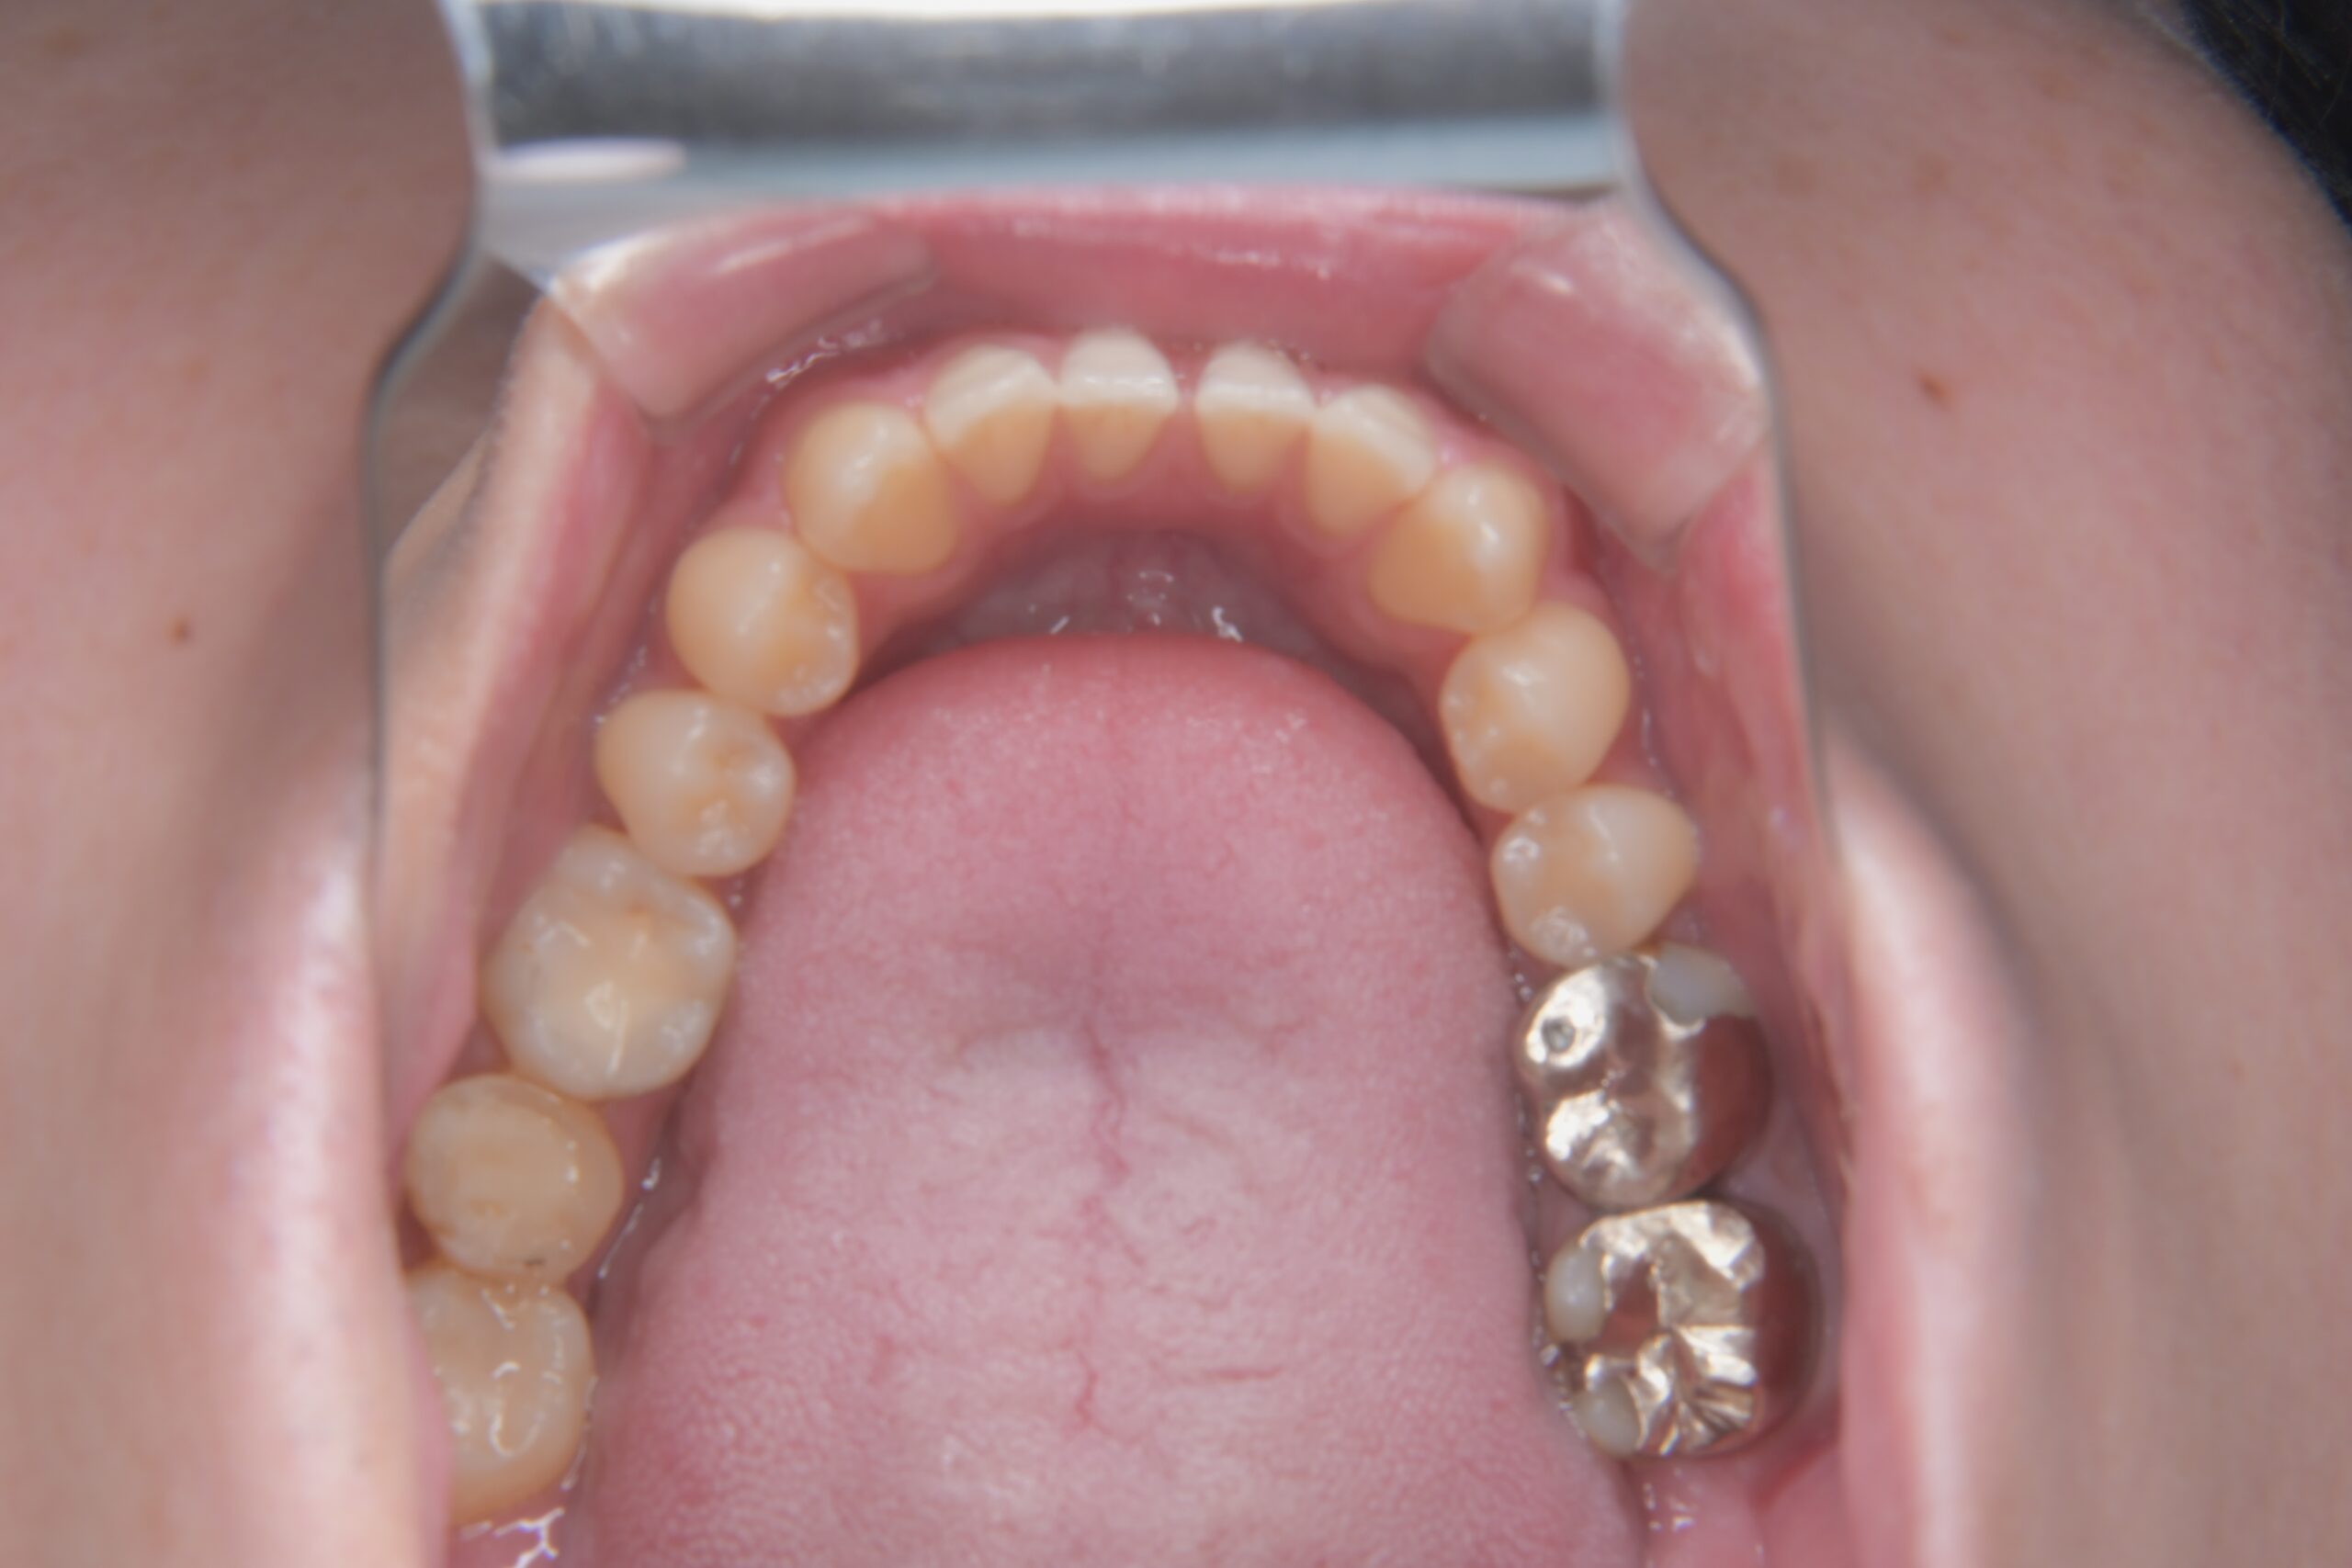

Before